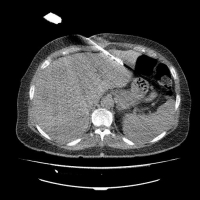

Images: CT-guided radiofrequency ablation of a lung metastasis (arrow, left), CT-guided microwave ablation of a liver metastasis (right).